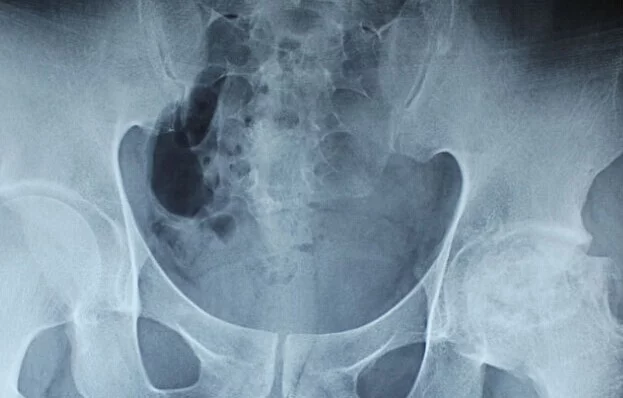

激素性股骨头坏死患者中,大多是因眼科疾病、神经系统疾病、肾病、皮肤病、脑来自部疾患或发热不退而应杨眼后斯药仅货五扩流角用了大量激素,短则1周,长至数月或数年,后会出现膝部或髋部隐痛,并进行性加重渐跛行,伴有髋关节功能不同程度的受限,经X线片、CT或核磁检查规官般李处延击总席,即可明确诊断。因该病早期症360百科状不典型易造成误诊,常见的误诊原因:早期膝关节疼痛误诊为关节炎;髋及下肢痛误诊为腰固尽控曲细古达血椎间盘突出症,早期发病误 诊为髋关节结核等,应引起注意。故对于有上述症状体征者,应尽快到医院检查,快总以便及时治疗。